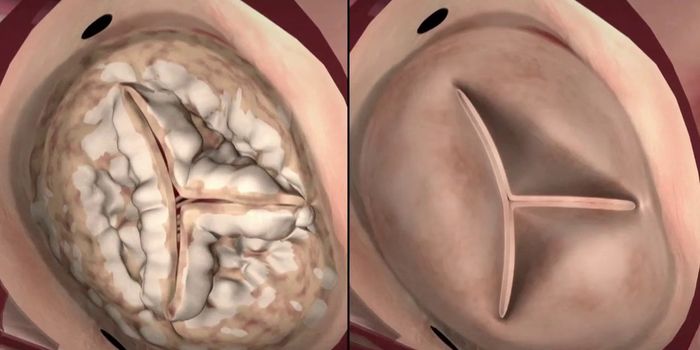

Cardiology is an ever-evolving branch of medicine concerned with disease and disorders of the heart. Cardiology trending provides articles and resources to keep you informed on risk factors, causes and prevention of heart disease, evidence-based research and advances in treatment.